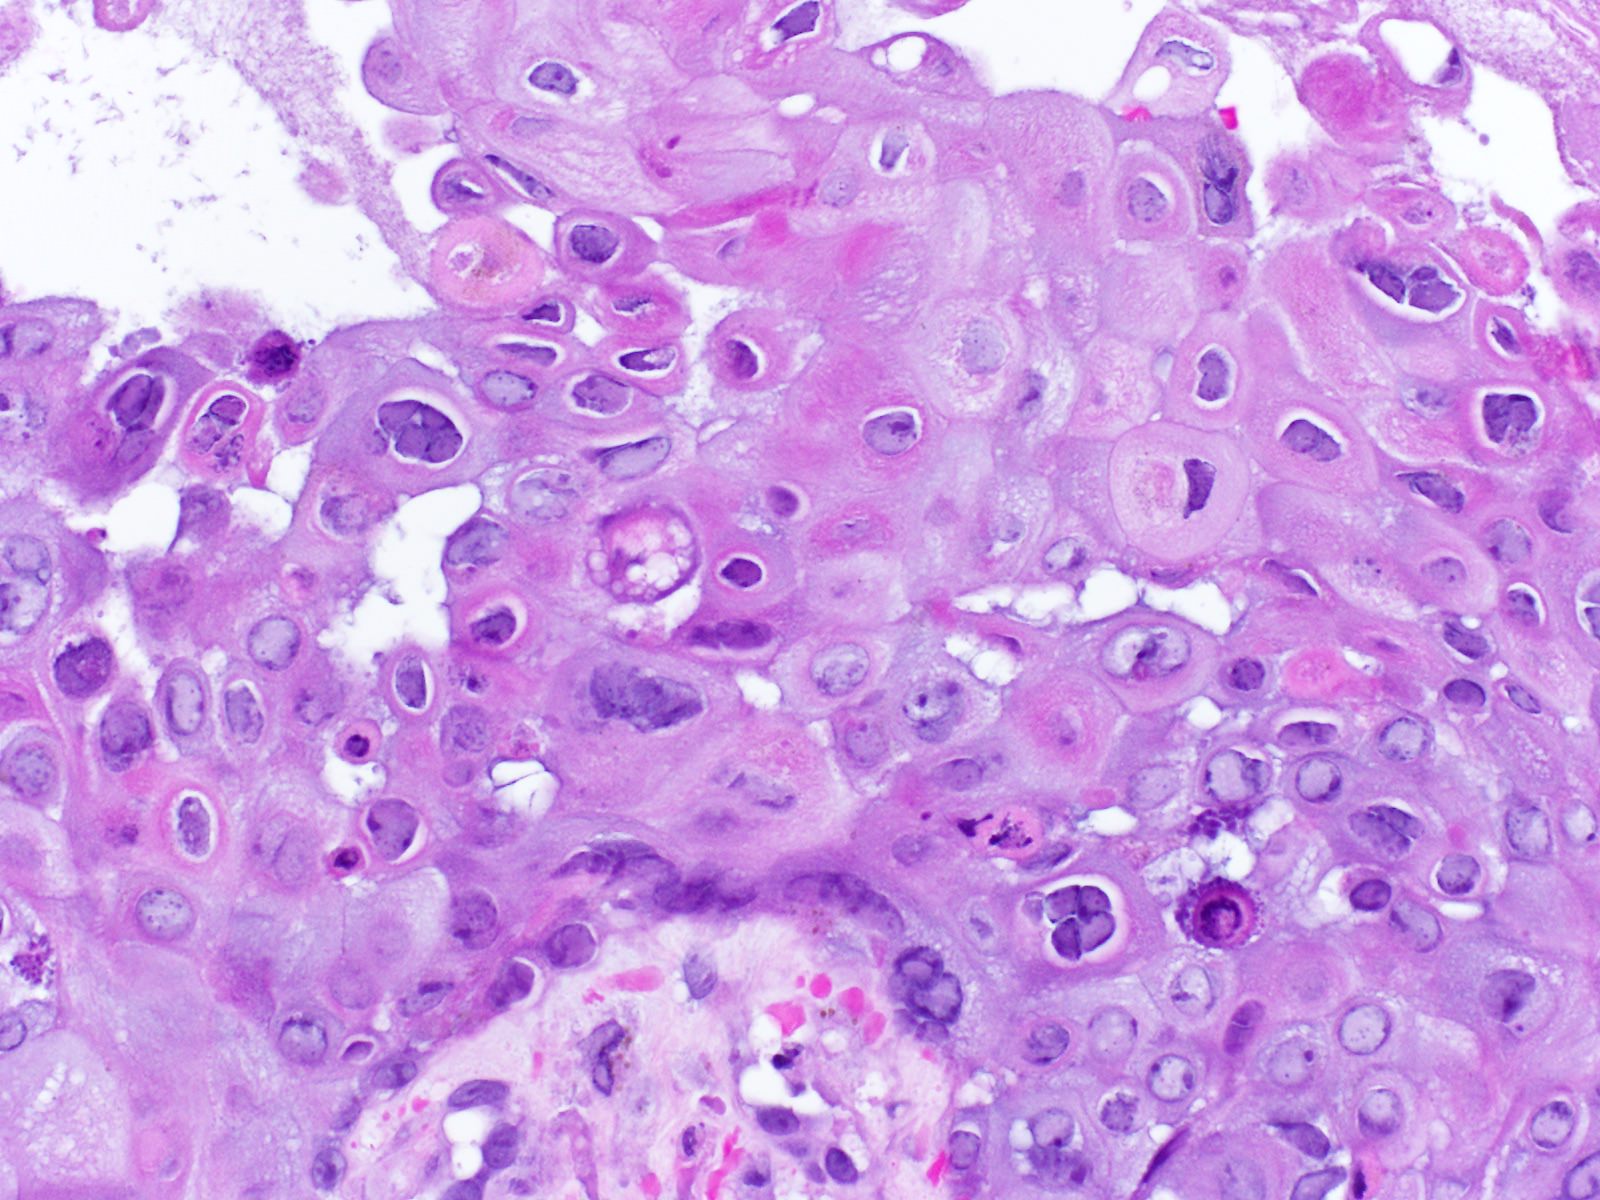

Медицинские снимки и изображения опоясывающего герпес вируса

Раздел: Фотодневник открытий